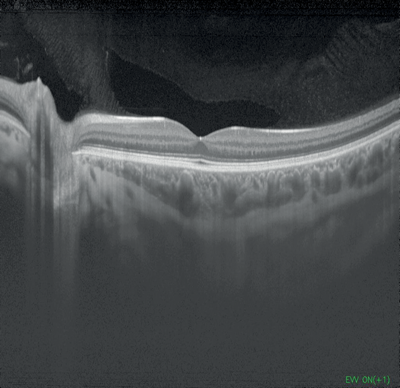

Figures 1-4: Swept-source OCT (DRI OCT-1 Triton, Topcon) images of healthy eyes that clearly delineate features in the vitreous, including area of Martegiani, bursa premacularis and posterior hyaloid, right through to the sclera, in the same single scan.

Figure 5: Colour fundus photograph of healthy eye taken

using swept-source OCT (DRI OCT-1 Triton, Topcon).

Topcon’s newly-introduced swept-source DRI OCT Triton can capture 256 B-scans in less than three seconds, with high speed scanning of 100,000 A-scans per second and a 1050nm wavelength which can penetrate easily through cataracts and haemorrhages. It features widefield 12 by 9mm scan screens for both glaucoma and macular pathology in one scan, with consistent signal strength from cortical vitreous to the sclera with an average of up to 128 times, automatic detection of seven retinal layers, as well as 2.6 micron digital resolution. The DRI OCT Triton has a built-in high resolution colour fundus camera, fundus guided acquisition (SmarTrack) and the option of an anterior imaging module. The Triton Plus also features fundus autofluorescence and fluorescein angiography, and an OCT angiography module is currently under development.

Swept-source OCT is an important part of the future of ophthalmic imaging, argued Richard F Spaide (New York, USA), speaking during the 2014 Retina Subspecialty Day imaging session. Swept-source OCT uses a frequency-swept light source and photodetectors as well as a longer centre wavelength, the latter improving penetration through tissue and allowing simultaneous imaging of the vitreous and choroid. Sensitivity fall-off with increasing depth is less than that seen with spectral domain OCT. The main attributes of swept-source OCT are deeper range of imaging, vitreous imaging and faster scanning speed.

In contrast to a broadband super-luminescent diode, spectrometer and high-speed line-scan camera utilised for spectral domain OCT methodology, swept-source OCT uses a wavelength-sweeping laser and a dual-balanced photodetector. The wavelength tunable laser light source allows for a much higher image acquisition speed than conventional SD OCT and produces better light penetration into the deeper tissue and hence improved visualisation of the choroid, including assessment of choroidal volume.